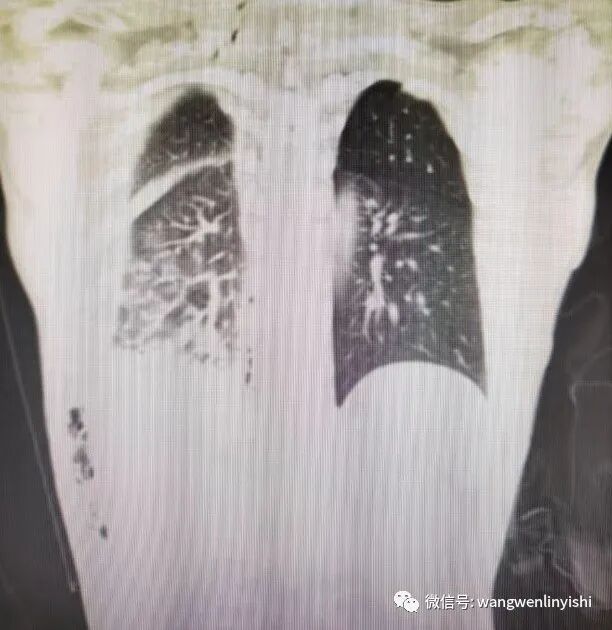

今天的患者为男性,35岁,因外伤3小时急诊入院。患者入院前3小时从高处坠落,右侧胸壁着地,伤后局部剧烈疼痛,呼吸时加重,伴呼吸困难。入院查体:右侧胸壁下部大面积皮肤擦伤,局部有明显压痛,骨擦感明显。右侧呼吸音明显减弱。身体其他部位未见外伤。术前行影像学检查,提示右侧第6、7、8、9、10肋骨骨折,所有五条肋骨在腋中线到腋前线之间均有一处骨折,全部离断,第9、10肋骨在后肋靠近脊柱旁均有粉碎性骨折,骨折端完全离断。右侧血气胸。术前诊断为重度胸外伤,肺裂伤,多根多处肋骨骨折,血气胸。

(右侧第9、10肋骨后肋粉碎性骨折,每条肋骨后肋都有两处骨折,中间部分完全离断)